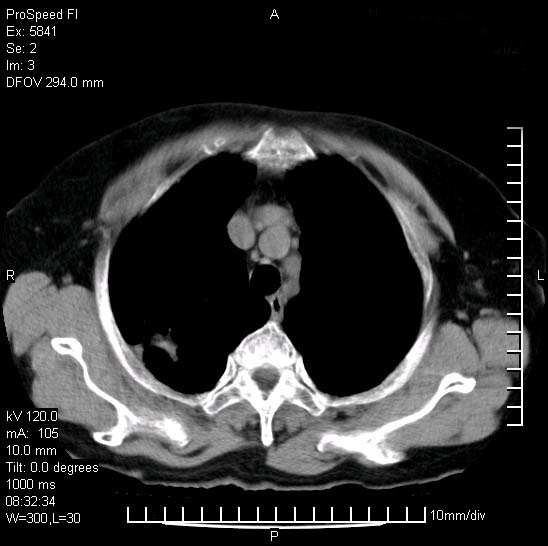

胸痛,咳嗽,气短一周,无发热。右上肺见一结节灶,边缘刺角,内见多个小钙化结节。考虑结核球?肿瘤? 余无异常没有上传。

考虑右肺上叶继发性肺结核,结核球形成。

胸膜是受侵的,考虑感染,结核球可能性大

考虑结核球,并胸膜局限性增厚!!